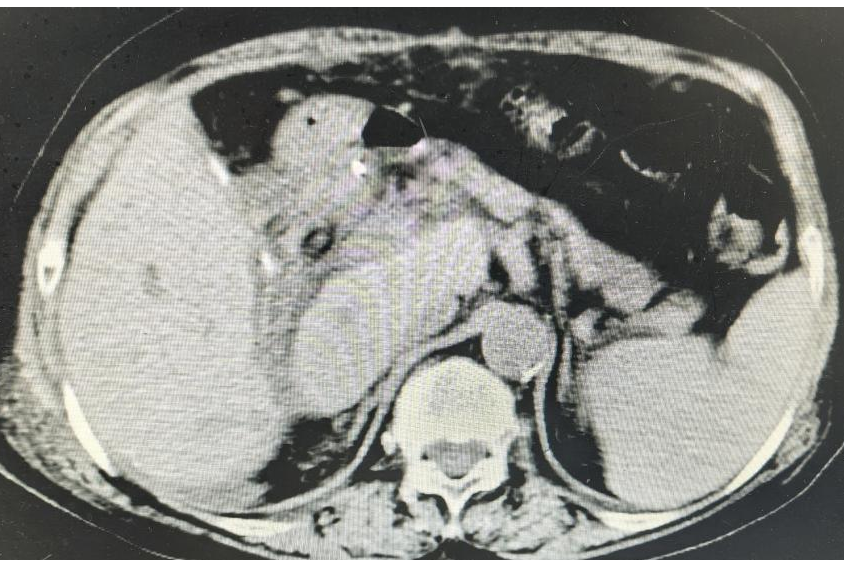

术前CT显示

同龄的谭阿姨,隆回北面鸭田人,上腹疼痛3天来院。她的情况更棘手:肝内外胆管多发结石和急性胆管炎之外,还有2型糖尿病、高血压病3级(高危组)。手术考验的不仅是外科医师的技术,还有麻醉和围手术期管理的整体功底。

3月7日,同样的腹腔镜方案:腹腔镜下左肝外叶切除,联合胆道镜胆总管切开取石和T管引流。手术顺利,术后血糖血压稳稳当当,谭阿姨恢复不错,如期出院。